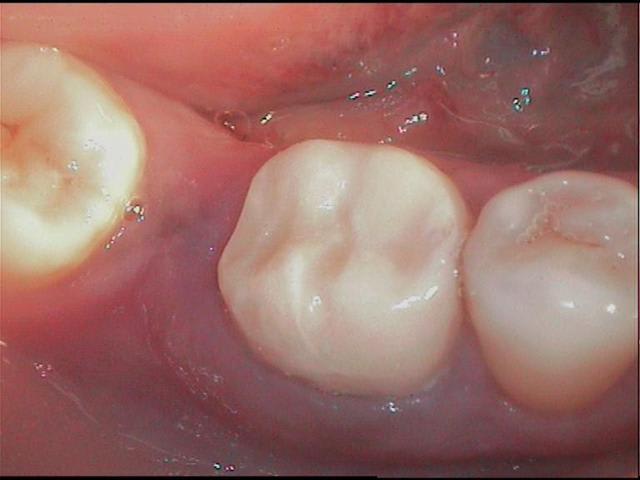

en déposant délicatement le compo, je trouve donc ça (photos) et c'était plutôt bien fait, j'imagine que le prat a craint d'avoir trop de contraintes canalaires avec un ancrage différent, moralité les contraintes ce sont accumulées au tiers cervical et c'est là que ça a cassé.